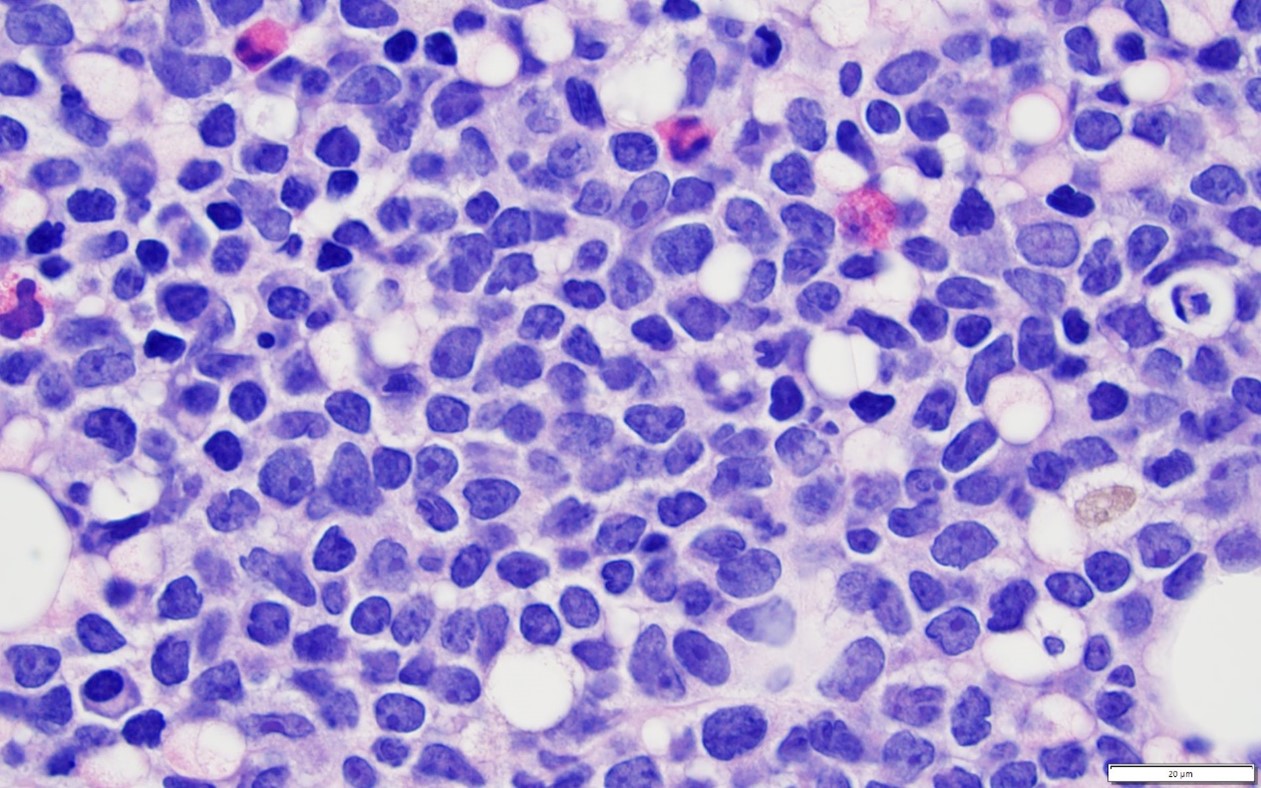

Диагностика лимфомы Ходжкина с помощью ПЭТ и КТ